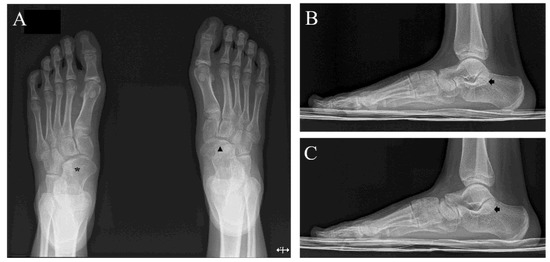

Bilateral Multiple Tarsal Coalitions (Talonavicular and Talocalcaneal Coalitions) with Recurrent Ankle Sprain in an Adolescent

2. Case Report